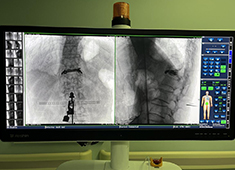

平板C臂具备众多优势,在图像质量、成像速度、幅面视野、剂量方面均优于影增C臂。在过去的15年里,C型臂X光机市场已经从图像增强器(IIs)转向平板探测器(FPD)。虽然目前仍有许多医院使用的是影增C臂,但其将要被平板C臂...